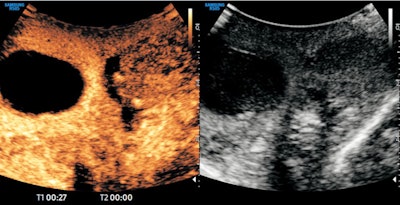

Ultrasound capabilities were "ever-evolving," with many different techniques combining to achieve a patient diagnosis, so-called "multiparametric" ultrasound, he continued. Moreover, this was accomplished at lower cost and patient morbidity than any other imaging modality.

He described the benefits and growing capabilities of ultrasound, including contrast-enhanced techniques and "exciting" developments in hepatic care, for measuring the quantity of fat and stiffness in patients' livers.

Contrast-enhanced ultrasound demonstrates testicular infarction in a case of spermatic cord torsion. Image courtesy of Prof. Paul Sidhu.In some countries, such as China and Russia, the trend was for ultrasound practitioners "only to do ultrasound, nothing else."